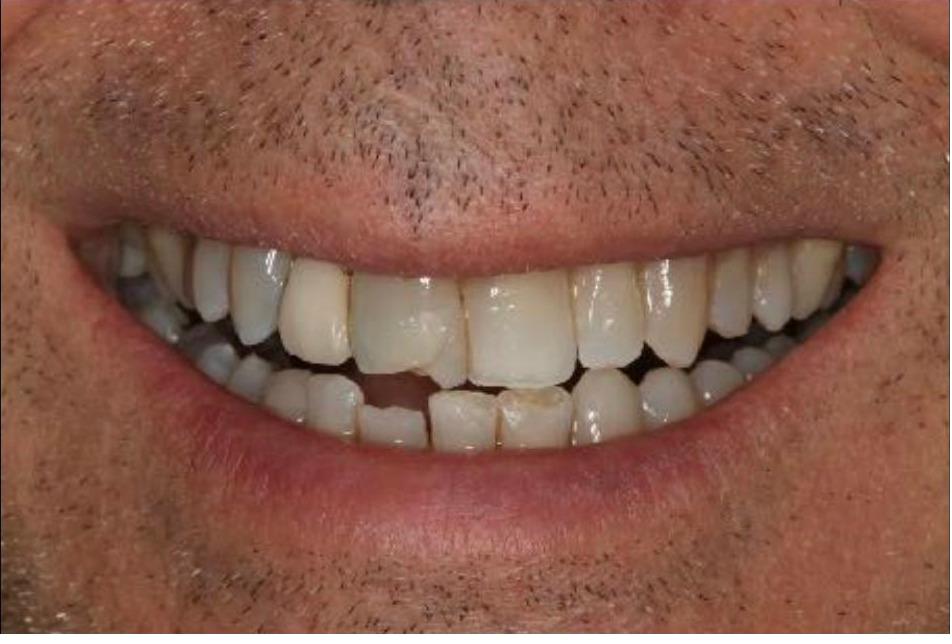

This patient had significant wear and chipping of his teeth. To restore his dental esthetics and function, following orthodontic therapy I fabricated crowns for his front teeth to restore the proper length, contour, and esthetics. He was thrilled with the result of our interdisciplinary care.

This patient had numerous cavities and missing teeth and wanted to improve his dental health and esthetics. Working closely with a periodontist who placed implants in the sites of the missing teeth along with my laboratory technician, I fabricated a combination of crowns on his upper natural teeth and implant crowns to restore his dental health, bite, function and esthetics. He was extremely happy with the result!